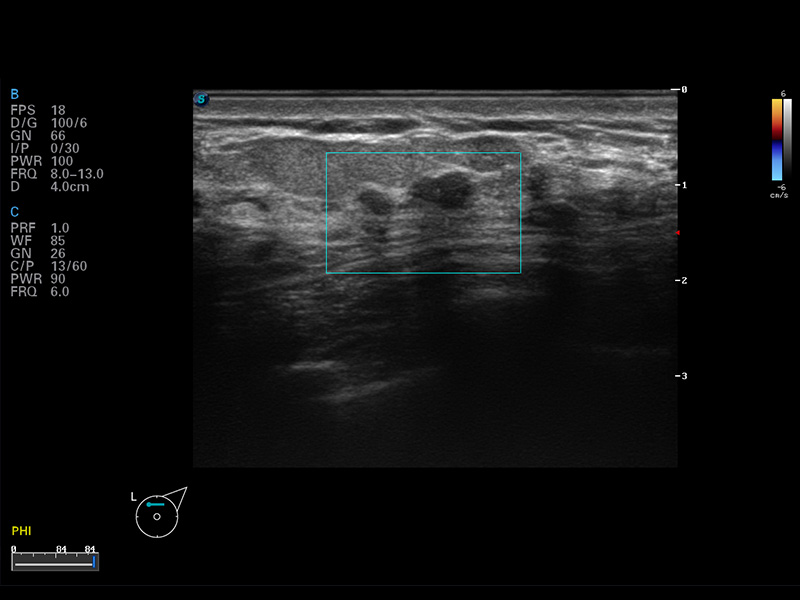

S8 EXP便携式彩色多普勒超声诊断仪是乐玩lewin国际研发的高端全身应用型便携彩超。高通道的VIS平台融合可视化(Visual)、智能化(Intelligent)和人性化(Smart)的特点,配以乐玩lewin国际自主研发生产的探头大家族,使您能够快速、准确的获得病人信息,提高工作效率的同时减轻疲劳。

μ-Scan微米成像